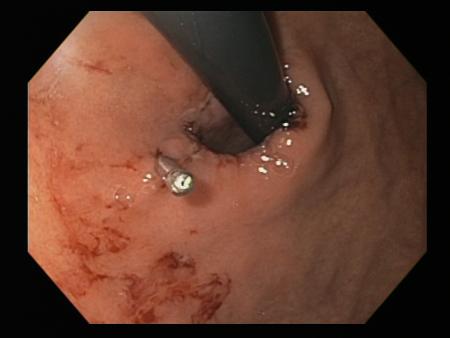

[Figure caption and citation for the preceding image starts]: Mallory Weiss tear after application of through-the-scope clip results in haemostasisFrom the personal collection of Douglas Adler; used with permission [Citation ends].